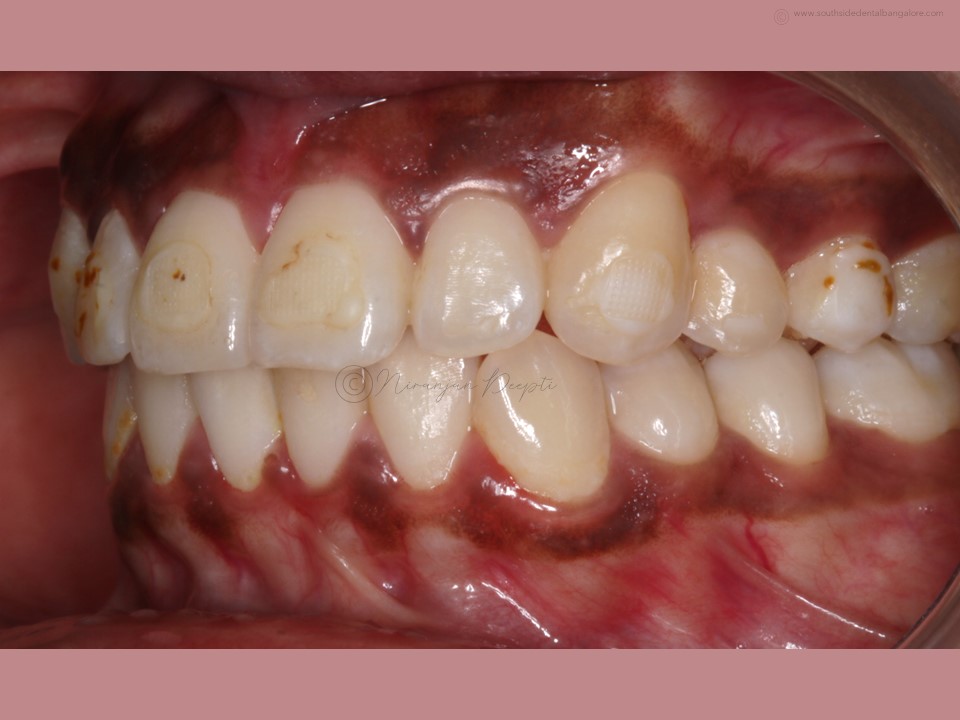

Polishing of teeth after the debonding of braces is a crucial step in the orthodontic treatment process.

- Smoother Surface: Braces leave adhesive residue and small imperfections on the tooth surface. Polishing helps smoothen these areas, reducing the risk of plaque accumulation and making it easier to clean teeth effectively.

- Minimizes Staining: Residual bonding materials and rough surfaces can attract stains, affecting the appearance of your smile. Polishing removes these stains and restores the natural luster of your teeth.

- Scaling: Before polishing, your orthodontist may perform scaling to remove any hardened plaque or calculus deposits that have accumulated during the braces treatment.

- Polishing: Using a specialized dental tool, your orthodontist/dentist will carefully polish each tooth surface to remove any remaining adhesive residue and smooth out imperfections.